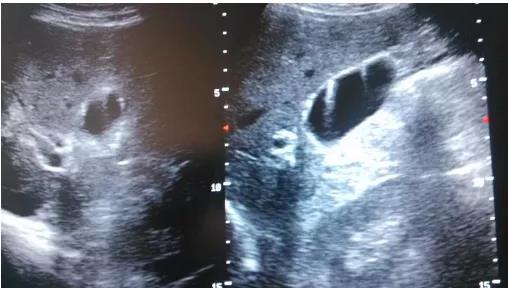

(▲膽囊真性息肉)